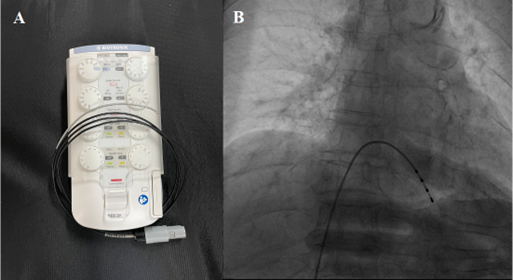

Bộ máy tạo nhịp tim tạm thời (A) và điện cực tạo nhịp tim đã được đặt

ở trong tim để tạo nhịp tim cần thiết cho sự sống.

Bước đầu, bệnh nhân được đặt 1 máy tạo nhịp tim để tạm thời để duy trì nhịp tim cần thiết cho sự sống. Sau khi đặt máy tạo nhịp, bệnh nhân được chụp động mạch vành ngay sau đó, kết quả cho thấy tắc hoàn toàn động mạch vành (P).